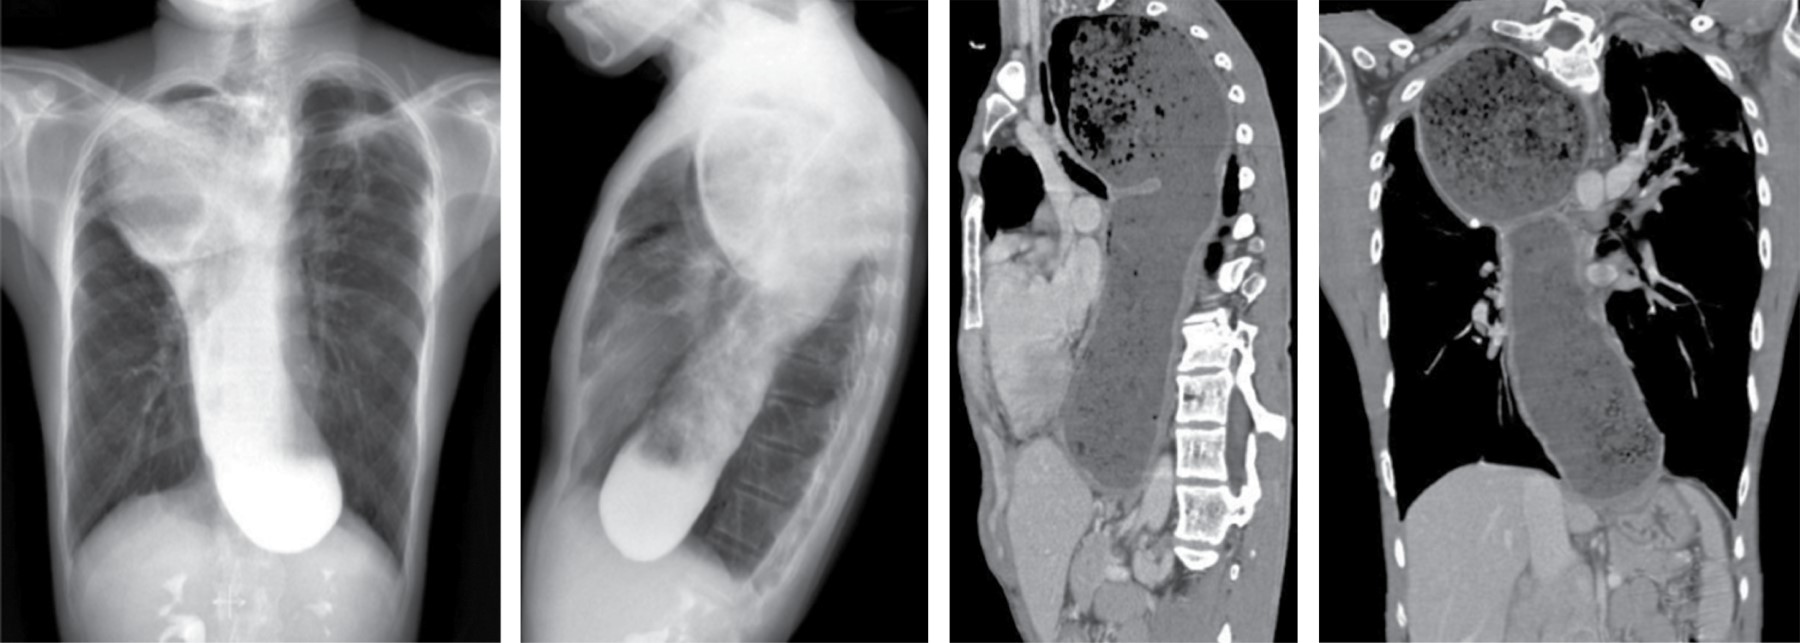

En la TC, típicamente se manifiesta como masas de atenuación de tejidos blandos que obliteran planos grasos mediastinales y encasilla o invade estructuras adyacentes. Sherrik y colaboradores8 identificaron dos patrones de invasión tomográfica: un patrón focal y un patrón difuso. El patrón focal (Figura 3) visto en 82% de los casos, se manifiesta como una masa con atenuación de tejidos blandos que con frecuencia calcifica (63%) y usualmente se localiza en las regiones paratraqueal derecha o subcarinal o en el hilio. El patrón difuso (Figura 4), visto en 18% de los casos como una masa infiltrante no calcificada que afecta múltiples compartimentos mediastinales. El patrón difuso ocurre en el estadio de otros desórdenes fibrosantes idiopáticos tales como fibrosis retroperitoneal.

Puede ocurrir con esofagitis y estenosis, carcinoma esofágico u otros tumores, mediastinitis fibrosante, esclerodermia, acalasia y leiomiomatosis. La marcada dilatación puede resultar en una masa mediastinal aparente en las radiografías. En pacientes con dilatación esofágica conocida, la tomografía puede usarse en la identificación de la masa (Figura 8).

La dilatación esofágica en acalasia y esclerodermia están usualmente asociados con grosor de la pared normal. Un nivel aire-líquido y comida retenida pude ser visible en pacientes con acalasia, estenosis o carcinoma, pero es menos común con esclerodermia. La dilatación esofágica está presente en 80% de los pacientes con esclerodermia y frecuentemente son asintomáticos.